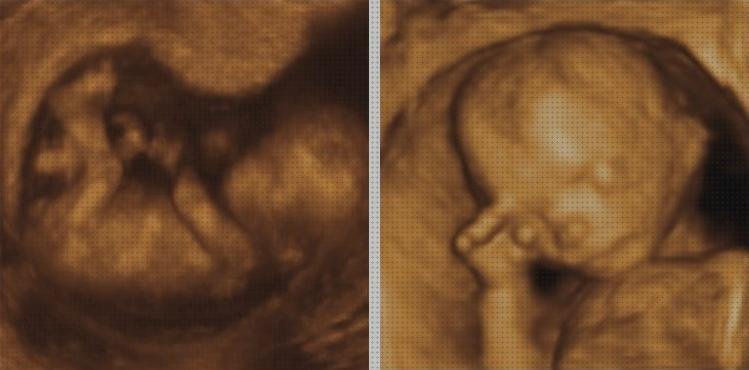

Una ecografía doppler es una investigación por imágenes que emplea ondas de sonido para exhibir la circulación de la sangre por los vasos sanguíneos. Las ecografías comunes también utilizan ondas de sonido para hacer imágenes de construcciones internas del cuerpo, pero no pueden exhibir la sangre en circulación.

La ecografía doppler funciona buscando ondas sonoras que se demuestran en objetos en movimiento, como los glóbulos rojos. Esto se le conoce como producto doppler.

Te dejamos aquí un gran vídeo de Ecografia Doppler Obstetrico

La ecografía doppler, completamente inofensivo e indolora tanto para la mamá para el bebé, facilita examinar datos muy relevantes del obstáculo: